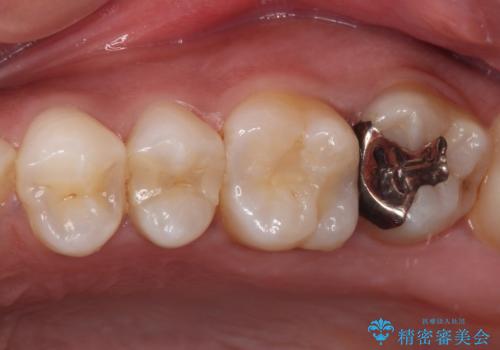

ゴールドインレーは銀歯のインレーやセラミックインレーと比べ、「技工操作の精度が高く、適合が著しく良い」というメリットがあります。特に上の奥歯は歯科医師の操作が行いにくいため、「適合の良さ」は再治療のリスクを防ぐ上でとても重要な要素となります。

上の奥歯は金属色が見えることもないため、審美的な問題は全くありません。

咬み心地はとても良好で、全く違和感がなく、患者様には大変満足していただきました。